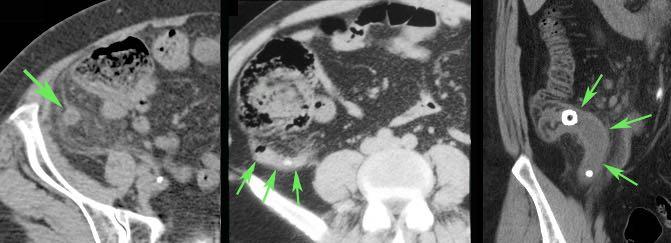

Người đàn ông 66 tuổi này nhập viện với đau bụng dữ dội kèm viêm phúc mạc toàn thể và CRP 550.

Siêu âm chỉ phát hiện quai ruột non giãn, CT được thực hiện với nghi ngờ thiếu máu mạc treo.

CT cho thấy viêm ruột thừa (mũi tên) với đầu ruột thừa thủng và nhiễm bẩn bốn góc phần tư của khoang phúc mạc.